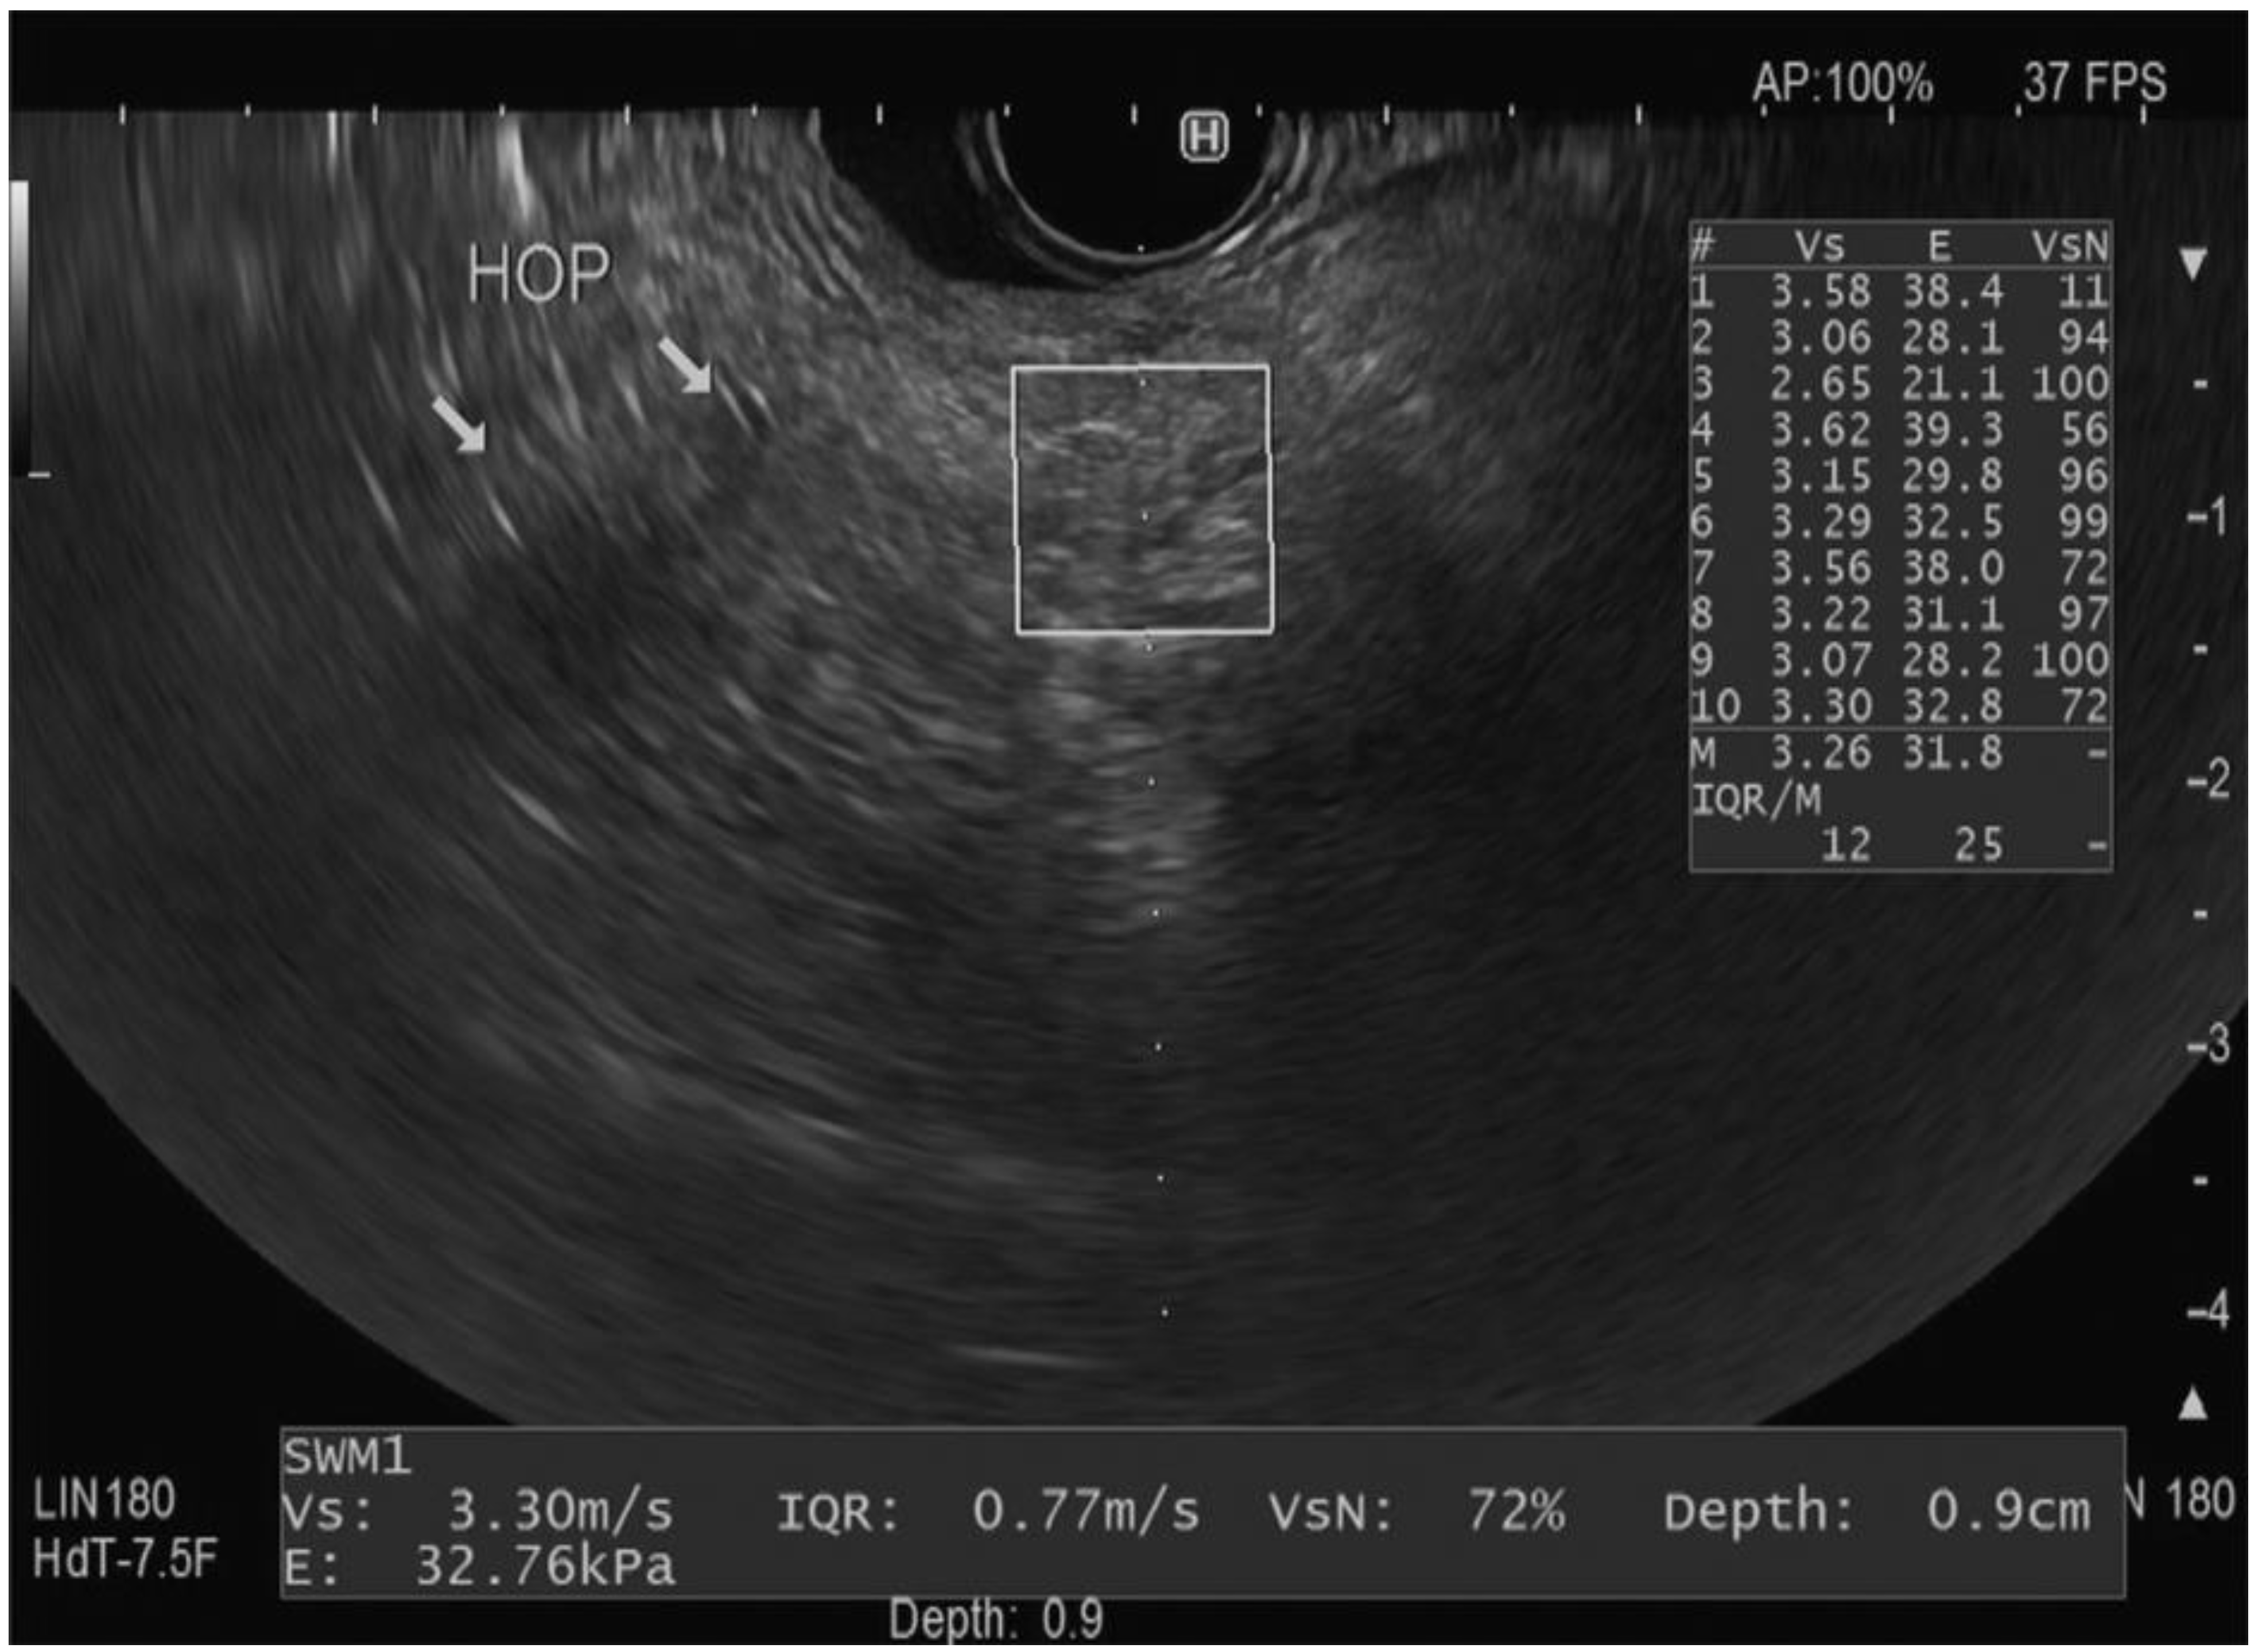

Each Vs measurement is accompanied by a reliability index (VsN). This index is expressed as a percentage and indicates the reliability of the measurement. The VsN helps in assessing whether external factors other than the shear wave velocity, such as artifacts or technical issues, might have influenced the reading. Prior research has established that VsN > 50% generally implies a reliable Vs measurement [10,32]. Furthermore, the software also provides another parameter, which is the Elasticity (E) of the tissue (measured by kilopascals “kp”), which represents the tissue’s stiffness [12]. It is measured by the Young module E = 3(Vs2ρ) [33]. By evaluating the median Vs measurement with its associated IQR and elasticity, clinicians can gain comprehensive insights into the mechanical properties and degree of stiffness/fibrosis of the pancreatic parenchyma. Figure 2 represents an example of EUS-SWE measurement in the head of the pancreas.

Figure 2.

Endoscopic ultrasound view of the shear wave elastography technique in a region of interest (square) in the head of the pancreas with measurements including the velocity (Vs), interquartile range (IQR), reliability (VsN), elasticity (E), and depth [10]. The arrows reflect the pancreatic parenchyma in the head of the pancreas.